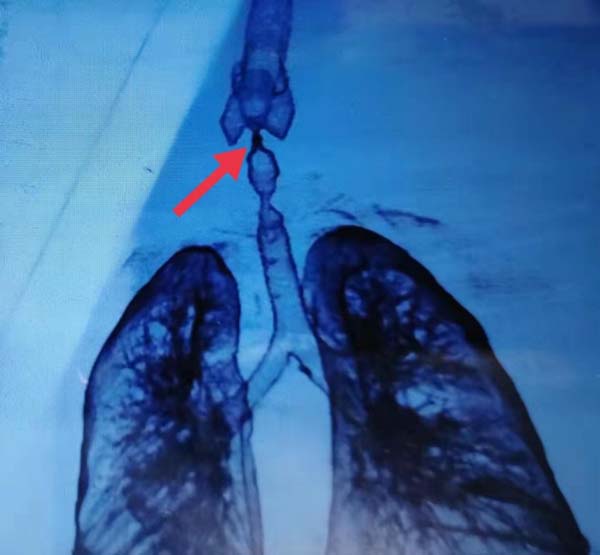

下图是患者2018年在当地医院做的支气管重建,气管上段几近闭锁。

4年间,患者多次求医未果,他最大的愿望就是拔除气切套管,开口讲话。经过多方询问打听,患者于今年7月6日慕名来到北京,在国家应急医学研究中心/应急总医院找到了周云芝主任。

入院后,周云芝主任仔细询问了患者的情况,迅速安排了气管镜检查,在进行第一次气管镜后发现患者的气管上段已完全闭锁!

在进行第一次气管镜检查之后,周云芝主任带领团队仔细分析了患者的情况。经过讨论制定了治疗方案:在CT引导下软硬镜结合对患者进行气道再通。